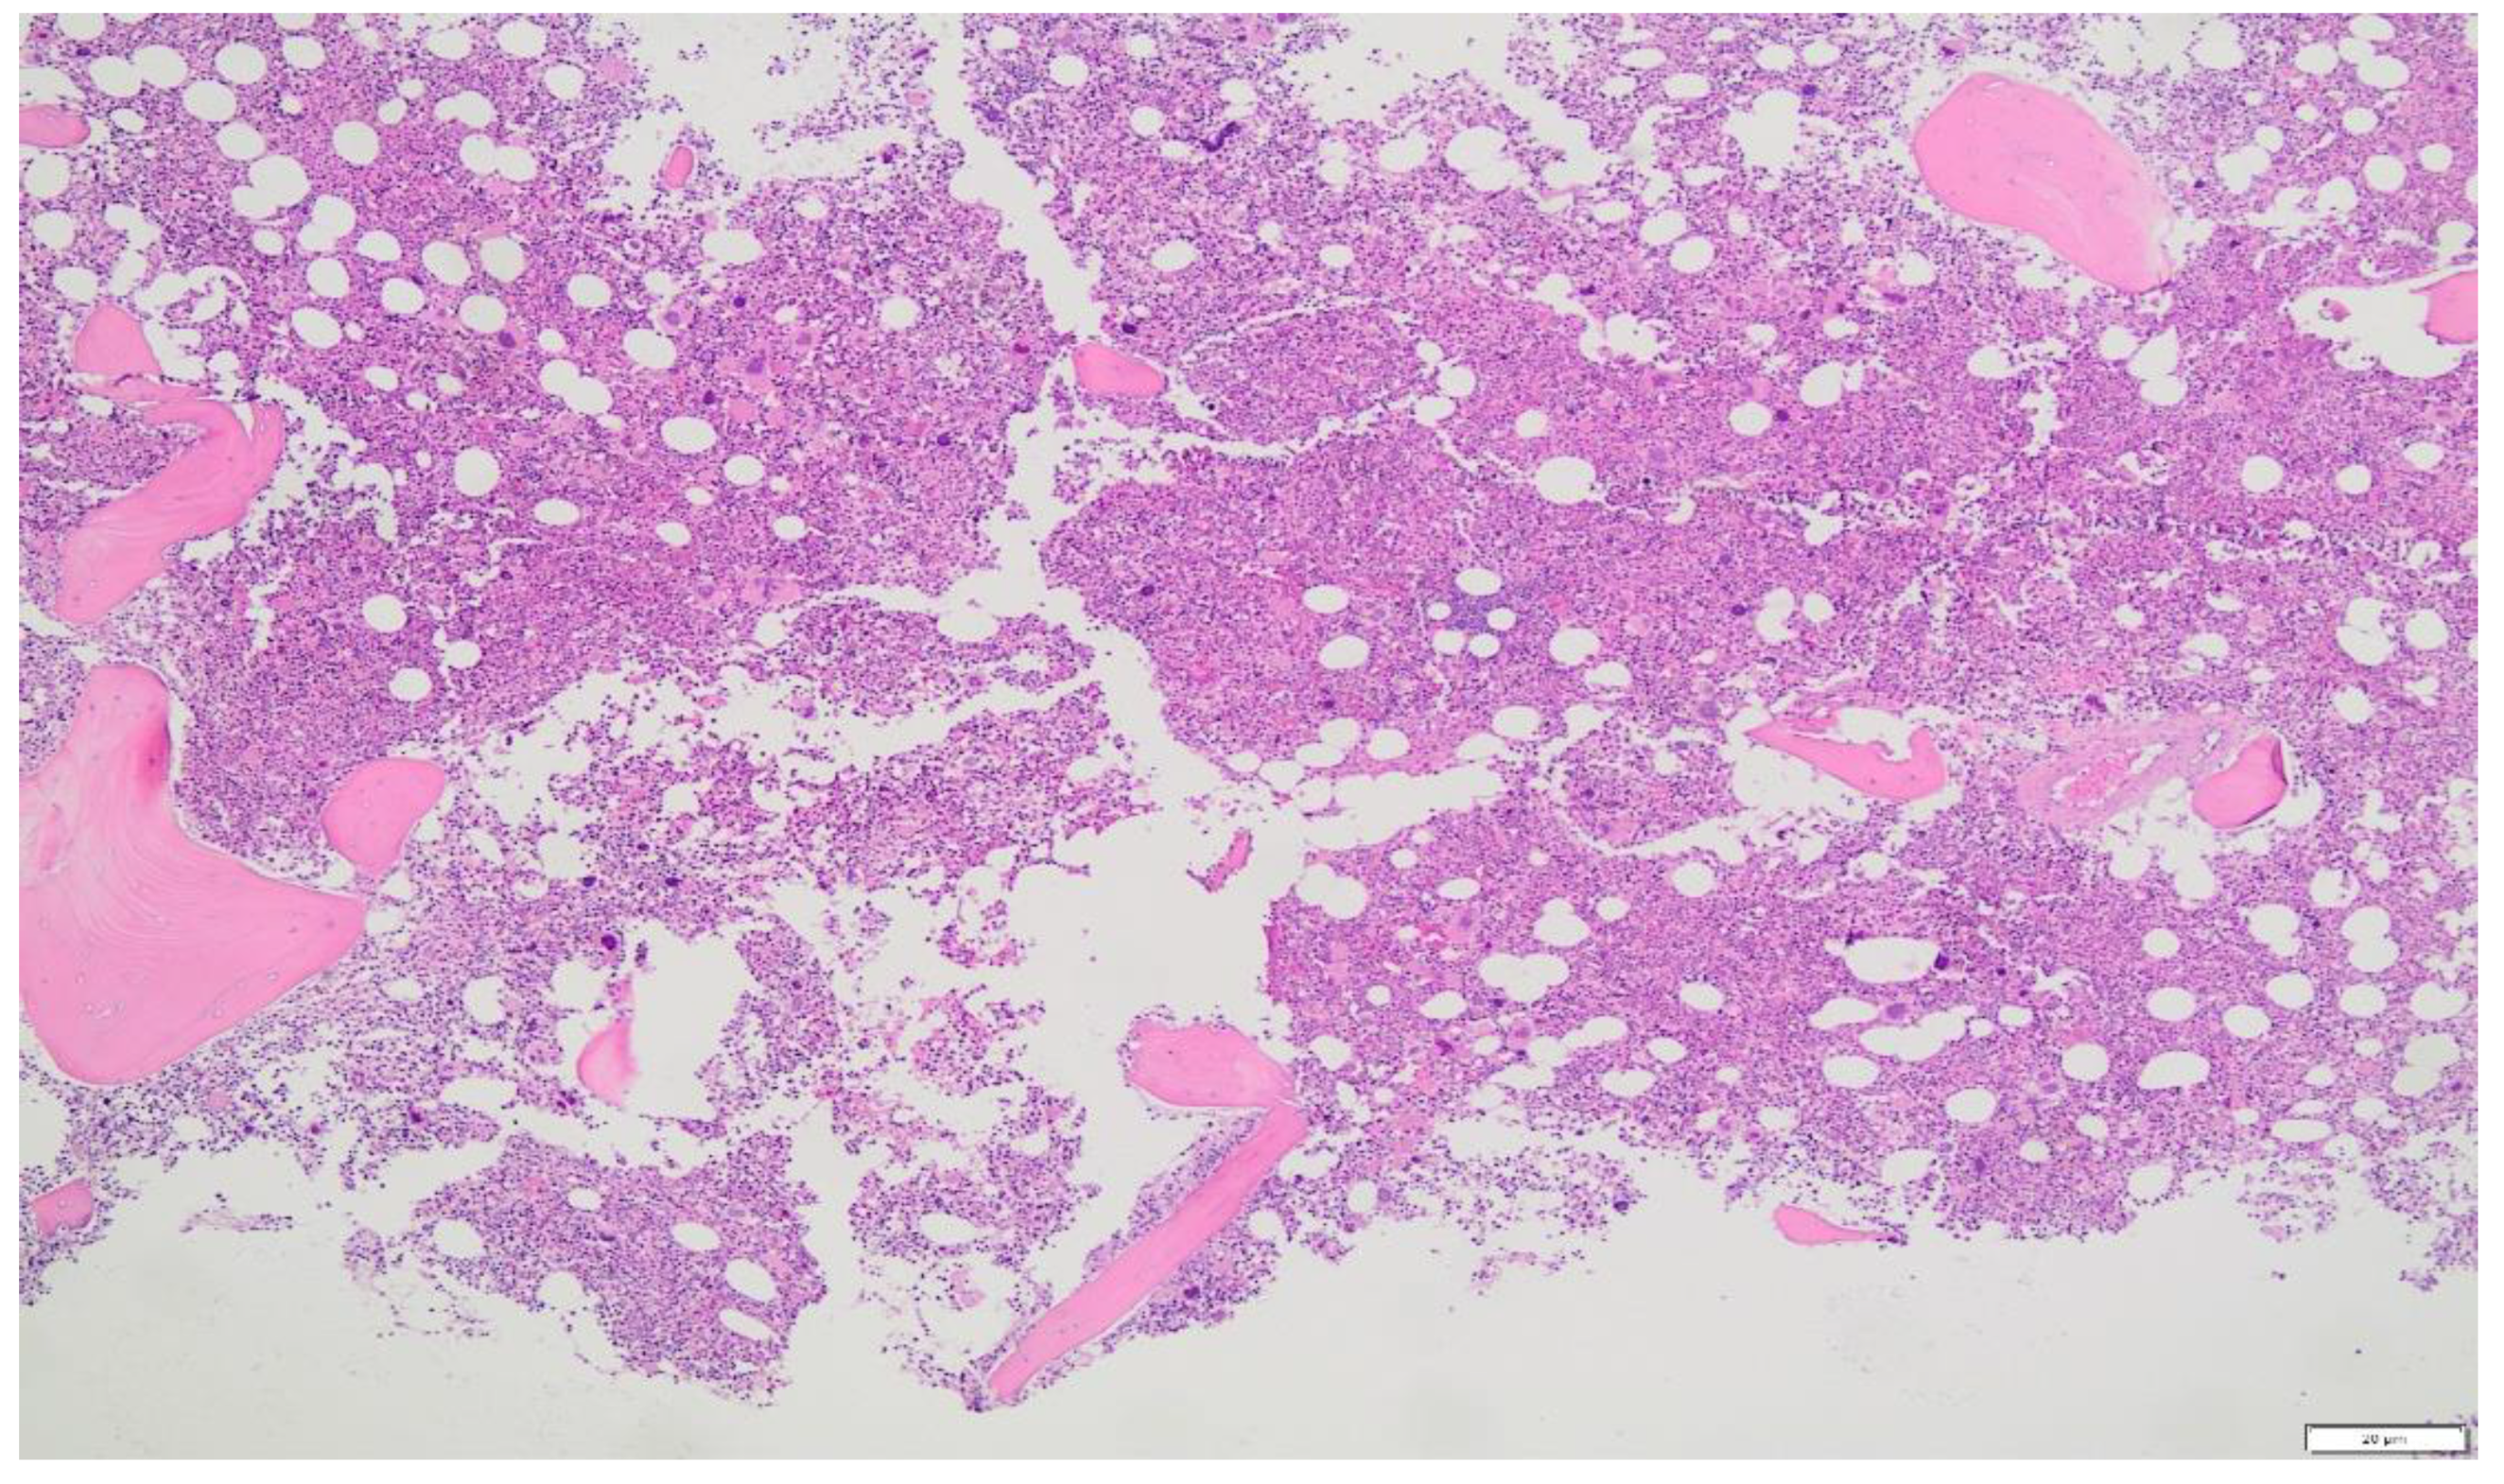

- A BM biopsy demonstrating trilineage growth (panmyelosis) and hypercellularity, with strong erythroid, granulocytic and megakaryocytic proliferation and pleomorphic adult megakaryocytes (differences in size).